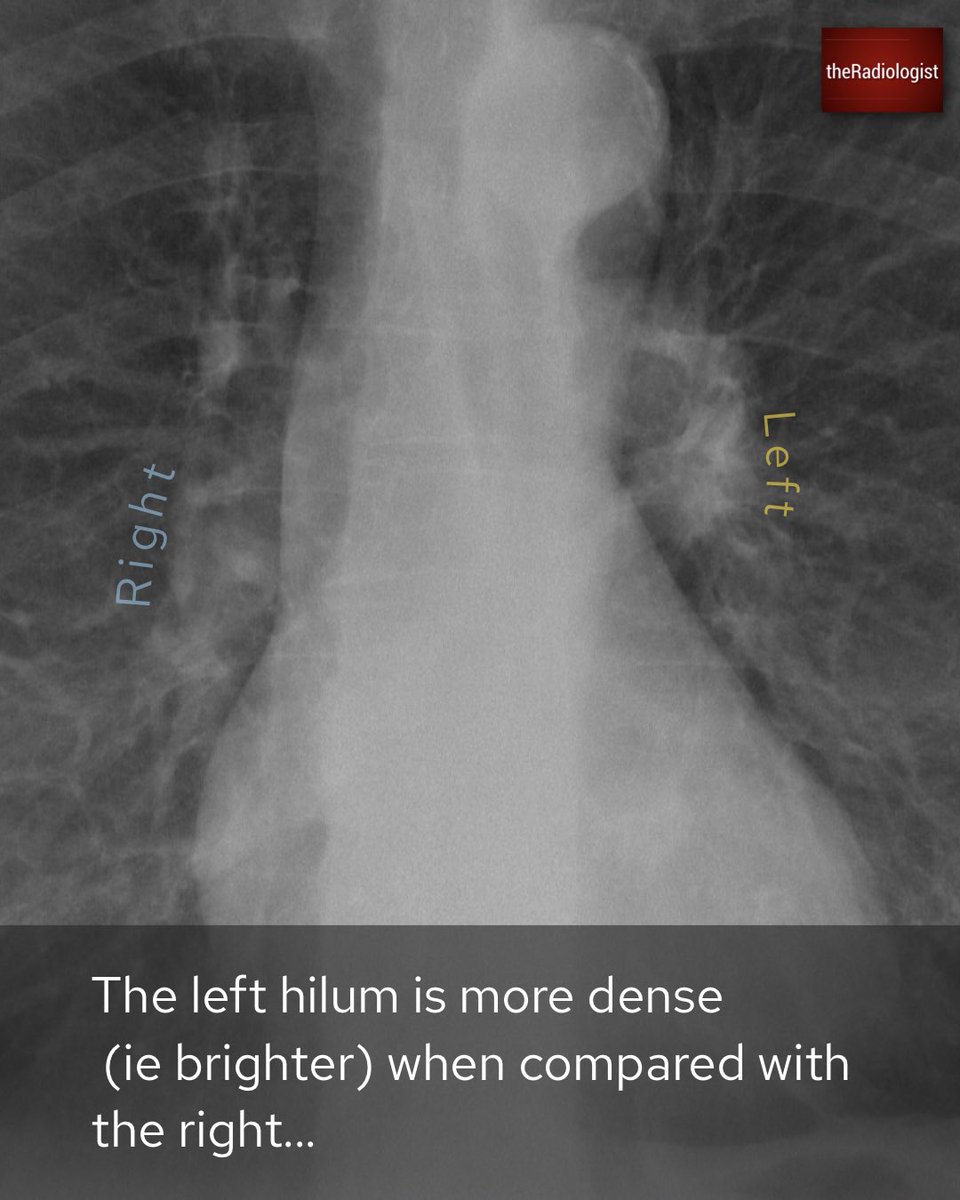

Female in her 50s presents with a cough

Explanation 1/3